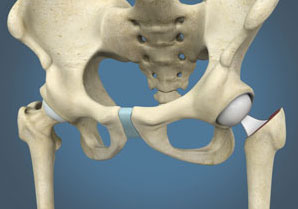

Unlike knees, primary osteoarthritis of the hips is not commonly seen in Asian populations. But, hip joints might develop secondary osteoarthritis following osteonecrosis (AVN), infections (including tuberculosis), trauma (ball and socket fractures) and childhood hip diseases such as developmental dysplasia (DDH), Perthe’s disease, etc. Inflammatory arthritis including ankylosing spondylitis and rheumatoid arthritis also commonly involve the hip joint. Fractures of the hip are common in elderly due to weakened bones (osteoporosis) and predisposition to falls. Traditional fixation of these fractures with screws or nails is not successful in all cases, and partial or total hip replacement is commonly required in these.

If only the ball (femur head) of the hip is affected, as commonly seen after hip fractures, only the femur head can be replaced in a partial hip replacement or hemiarthroplasty, and the native cup (acetabulum) is left untouched. The advantages of hemiarthroplasty over total hip arthroplasty are decreased surgical duration, morbidity and costs. However, the long term survivorship of hemiarthroplasty is limited (10-20 years), after which the native acetabulum wears out, and then it has to be converted into a total hip replacement. Hence, hemiarthroplasty is applicable only for elderly, low-demand patients, and total hip arthroplasty is the preferred surgery for younger patients (even if the acetabulum is healthy).